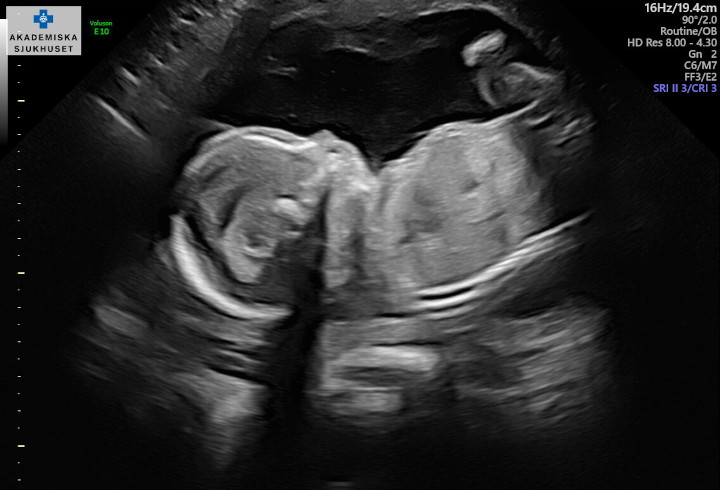

8 ben blir snart till 10

Cirka 13 juni 2024Den lilla flocken med Filippa, Martin och Dundra kommer snart utökas med ytterligare en familjemedlem, i form av en tvåbening. Storken har anmält en leverans till den 13 juni 2024 enligt säkra källor.